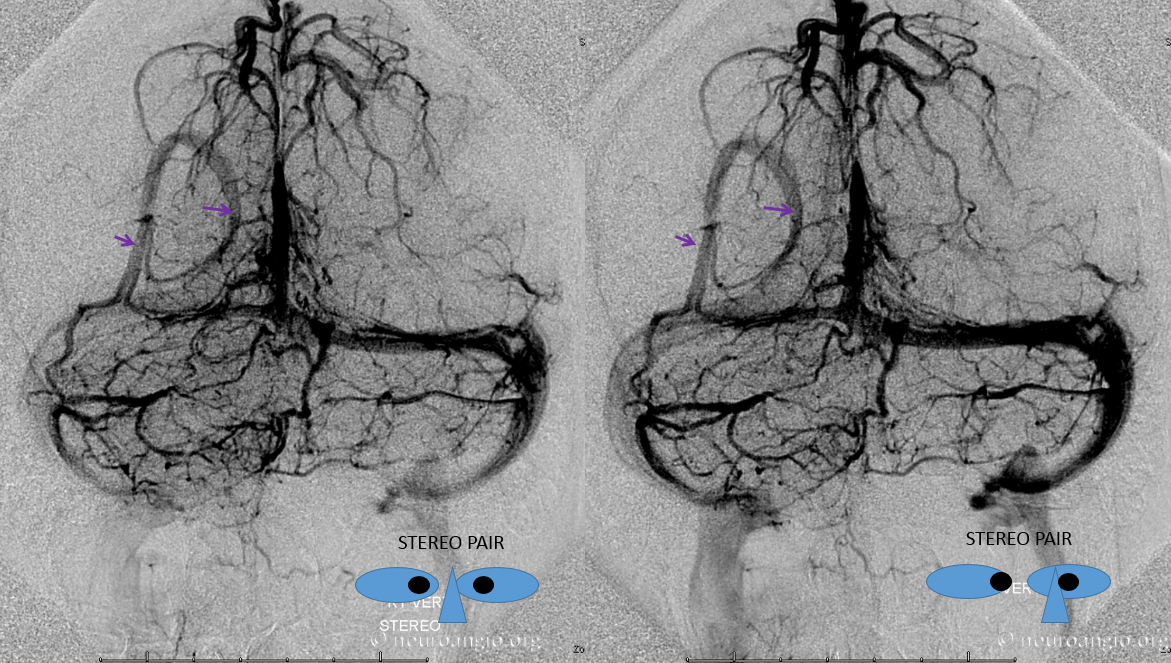

Here is an example of a right parieto-occipital sinus (purple arrows, stereo pair) which collects regional supratentorial and infratentorial veins, emptying into the transverse sinus. Again, this is really only of importance to a surgeon or interventionalist of a procedure in the area is being contemplated.